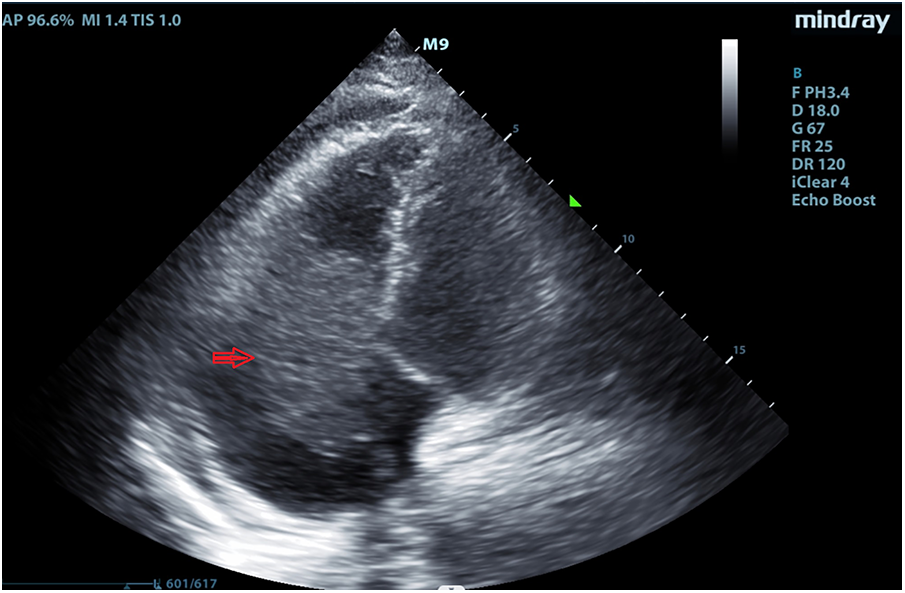

A 64 year-old man was admitted to our hospital on September 2, 2022, owing to symptoms of a tachycardia and shortness of breath. Physical examination at admission revealed the following: body temperature: 36.5°C, heart rate: 51 times/min, pulse: 51 beats/min; blood pressure: 102/68 mmHg, poor spirit, edema of the trunk, yellow sclera, slight cyanosis of the lip, no filling of the jugular vein, coarse breath sounds in both lungs, no enlargement of the heart boundary, arrhythmia, soft abdomen, and severe pitting edema of the lower limbs. Moreover, laboratory tests revealed the following: cardiac troponin I (cTNI) < 0.02 ng/ml (normal range: <0.53 ng/ml), creatinine-kinase-MB: 5.49 ng/ml (normal range: <5.0 ng/ml), myohemoglobin: 216.82 ng/ml (normal range: <110 ng/ml), D-dimer: 1214.27 ng/ml (normal range: <200 ng/ml), and B-type natriuretic peptide: 2460.72 pg/ml (normal range: <100 pg/ml). Electrocardiography indicated sinus rhythm, third-degree atrioventricular block, full-lead low voltage, QT interval prolongation, and borderline escape rhythm. Echocardiography revealed a hypoechoic mass extending from the right atrium to the right ventricle and obstructing the forward flow of the tricuspid valve. The size of the mass was approximately 66 × 40 mm (Figure 1). Computed tomography revealed the following: (1) irregular shape of the right heart, with the enhanced right auricle, right atrium, and ventricle exhibiting irregular clusters and relatively weakly enhanced areas. The CT value after enhancement was approximately 70–90 HU, while the larger cross-section was approximately 6.2 × 6.9 cm. The local boundaries between the lesion, pericardium, and left atrium were unclear, while the ventricular septum was irregular and thickened; (2) the filling of the superior vena cava and left and right brachiocephalic veins was not uniform; (3) the pulmonary artery and its branches in the upper, middle, and lower lobes of the right lung were poorly developed, while the local lumen was suspected to be uneven, exhibiting a few patchy and slightly low-density shadows. A suspicious low density shadow was observed at the edge of the upper and lower pulmonary arteries of the left lung; (4) the two lungs were dispersed with flaky shadows of increased density, the volume of the lower lobe of the left lung was reduced, a dense shadow was present in some lung tissues, and the enhancement was visible; (5) the bronchial segment of the left inferior lobe of the lung was slightly narrowed, while part of the bronchus of the left inferior lobe was unclear; (6) pericardial effusion, bilateral pleural effusion, left interlobar fissure, and adjacent lung hypoinflation; (7) the thoracic section of the esophageal wall was slightly thickened, approximately 0.4 cm; (8) swelling of left axilla, chest wall, and back soft tissue; (9) abdominal fluid, the local adipose space in the abdominal area was seen as lamellar and slightly high-density shadows; (10) multiple small veins in inferior vena cava and right lobe of liver were developed in advance; and (11) the adipose space in the abdominal cavity was blurred, with multiple pieces being increasingly flocculent, while the fascia around both kidneys was thickened (Figure 2).

Figure 1

Echocardiography revealed a hypoechoic mass extending from the right atrium to the right ventricle in September 2, 2022.